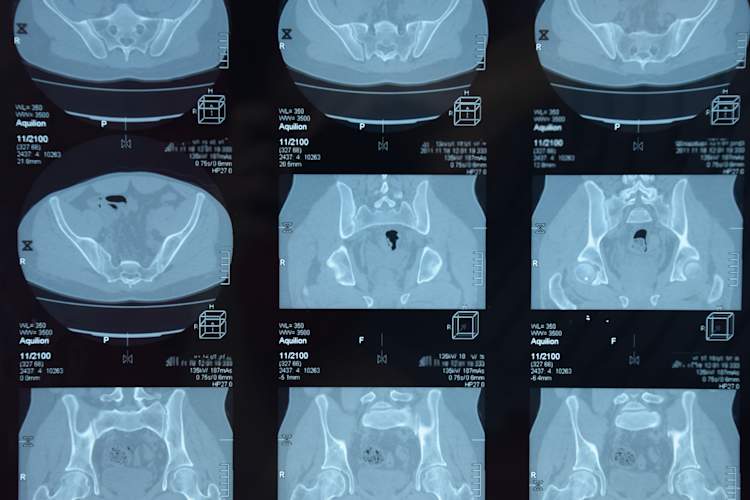

强直性脊柱炎的MRI表现

医生如何诊断

你认识有背部问题的人吗?几乎所有人,对吧?这就是强直性脊柱炎很难诊断的原因之一。我们是来帮助加快这一进程的。